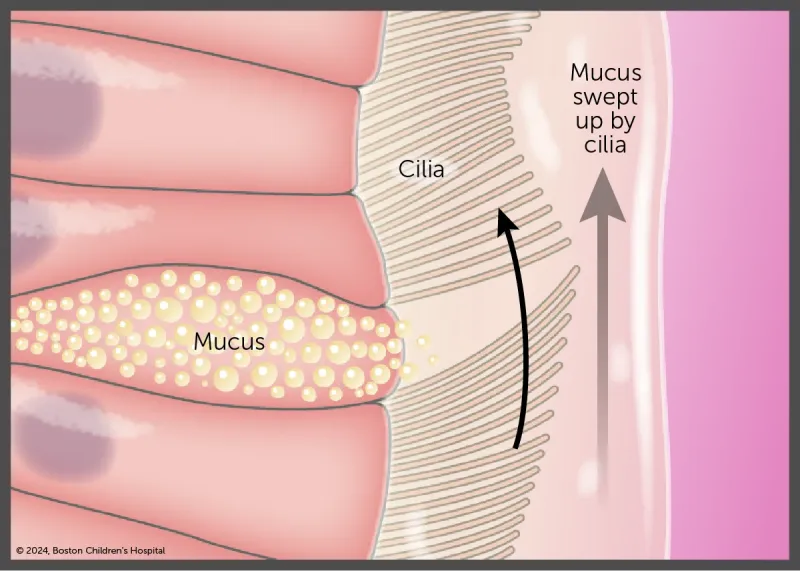

Primary ciliary dyskinesia (PCD) is a disorder of the cilia that line the entire respiratory tract, including the middle ear, sinuses, airway, and lungs, as seen in this illustration.